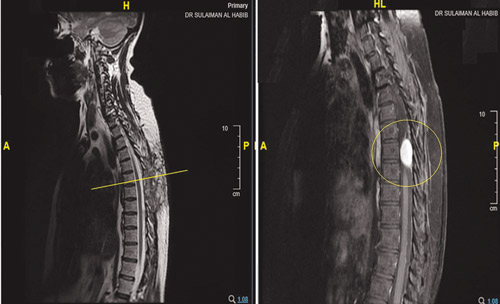

ذكر ذلك الدكتور مارون أبو ناضر استشاري جراحة المخ والأعصاب الحاصل على البورد الفرنسي وشهادة الاختصاص في المناظير الجراحية، والذي أضاف أنه وقت وصول المريضة للمستشفى، تم الاطلاع على تاريخها المرضى وإخضاعها لفحوصات دقيقة بالرنين المغناطيسي. وقال الدكتور أبو ناضر إن نتائج الفحوصات أبانت وجود ورم من النوع الليفي بطول 4 سم متمركز في الفقرة السابعة من العمود الفقري ومتداخل مع الأعصاب، مسبباً ضغطاً شديداً على النخاع الشوكي، وهو الأمر الذي يؤدي بطبيعة الحال إلى الإصابة بالشلل التام -لا سمح الله - في حال إذا تأخرت المريضة في العلاج. وأفاد الدكتور أبو ناضر أن الفريق الطبي المكون من جراحي المخ والأعصاب والعمود الفقري والقلب والتخدير، اتخذوا القرار بأهمية التدخل الجراحي العاجل، للحيلولة دون حدوث مزيد من المضاعفات، مشيراً إلى أن العملية استغرقت 4 ساعات تحت التخدير العام، وتم فيها الاستعانة بطاولة (Jackson Table) مصممة خصيصاً لتلك العمليات وتقنيات جراحة المنظار المجهرية (Pentero)، بالإضافة إلى استخدام آلات وأجهزة خاصة تُعرف باسم (Sonopet Ultra Sonic Aspirator)، والتي تعمل على إحداث اهتزاز لخلايا الورم وخلخلته وسحبه من مكانه دون تحريك النخاع الشوكي والشرايين الدقيقة بداخله، وذلك لتفادي حدوث الجلطات والشلل الدائم. وفي الختام أكد الدكتور مارون أبو ناضر أن جهود الفريق الطبي تكلَّلت بالنجاح -ولله الحمد - حيث تم استئصال كامل الورم من العمود الفقري والقفص الصدري، مشيراً إلى أنه تم معاينة المريضة بعد 24 ساعة من العملية وتبيّن اختفاء الآلام وتنميل الساقين والعمود الفقري والصدر ووجود تحسن كبير، مؤكداً على أن المريضة خرجت بعد 5 أيام من المستشفى وهي بصحة ممتازة بعد أن استطاعت الوقوف والمشي دون آلام.